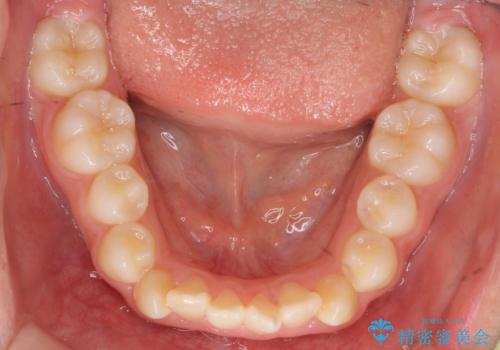

インビザラインチェンジで成功 インビザラインで八重歯の抜歯矯正

- かみ合わせを主訴に来院。

八重歯や、前歯のオープンバイト(開咬)の症状があり、マウスピース(インビザライン)矯正単独では治すのが難しい症状が複合していました。

八重歯や抜歯したスペースの閉鎖をワイヤー矯正で前半行い、治療後半は目立たないインビザラインでかみ合わせを調整しました。

ワイヤー矯正からインビザラインへの変更は、歯磨きも簡単になり、目立たず、さらにワイヤーと併用することで妥協せずしっかり治療結果も出すことができます。